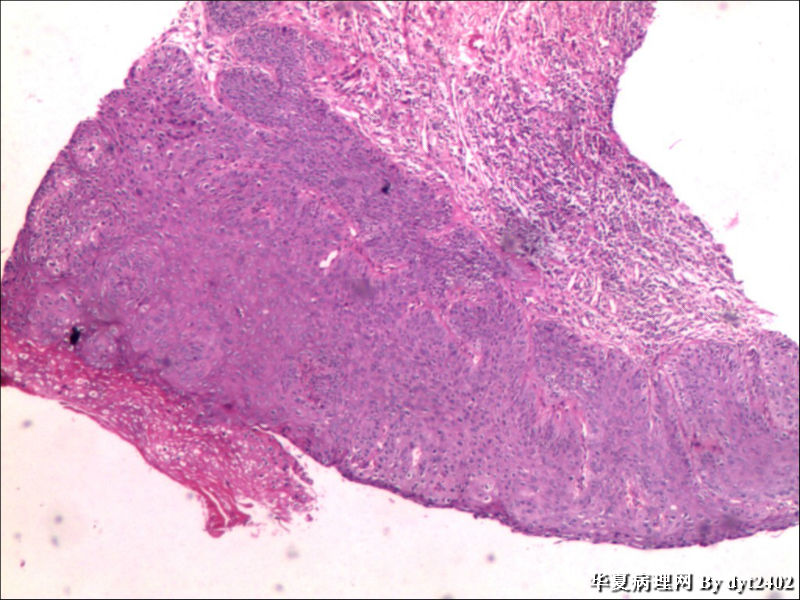

这样的外阴病变 发个原位癌是否合适?

图1

VIN III,做个银染或者标个免疫组化看一下基底膜是否完整。

看上去好像还完整 只是经常看见图5 那样结构的就觉得可能还有更重病变